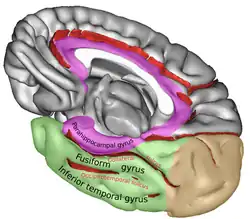

Giro fusiforme en amarillo, dentro del Lóbulo temporal. Vista interna del hemisferio izquierdo. | ||

El giro fusiforme se encuentra en el lóbulo temporal en la superficie basal del hemisferio cerebral, entre el giro temporal inferior por fuera y el giro parahipocampal por dentro. [1]

El giro fusiforme esta limitado por dentro por el surco colateral y por fuera el surco occípitotemporal lo separa del giro temporal inferior.